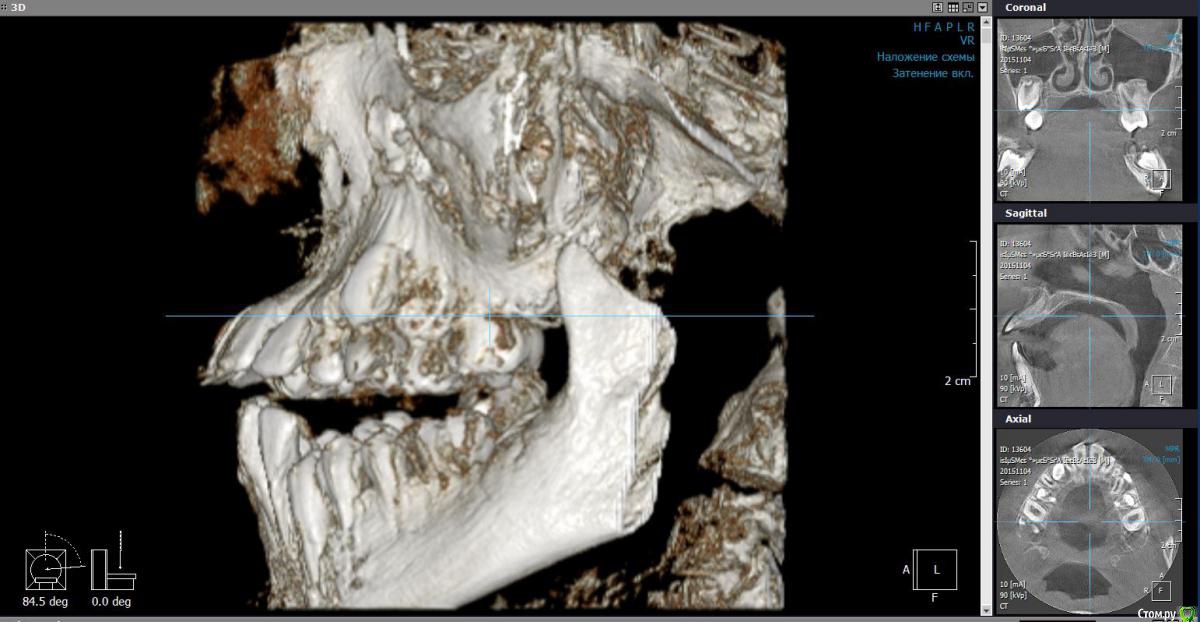

Monkey Опубликовано 27 апреля, 2016 Поделиться Опубликовано 27 апреля, 2016 (изменено) Коллеги! Прощу совета и помощи. Кто как справляется с выраженным 2-1. Парнишке 12 лет. Со слов мамы ни вредных привычек, ни родовой травмы не было. Опять же со слов мамы, есть серьезное искривление перегородки носа ( ЛОР сказал можно править только после 17 лет).Сейчас удалили зачатки 38,48. Ждем когда созреют 18,28.Как вести таких пациентов? и реально ли обойтись без хирургии? Когда начинать лечение и на каком аппарате?P.s. если у кого-то были похожие вылеченные случаи, буду благодарна за демонстрацию. Изменено 27 апреля, 2016 пользователем Monkey Ссылка на комментарий

Yana guapa Опубликовано 27 апреля, 2016 Поделиться Опубликовано 27 апреля, 2016 почему клкт делали с открытым ртом? в итоге проекции , которые вы выложили - не информативны. лучше "классика" - снимки (трг) , фото (причем полноценный набор:фас, профиль, профиль с улыбкой, обнажение резцов в покое...) это все имеет значение при составлении плана лечения и выбора методики. Ссылка на комментарий

Monkey Опубликовано 28 апреля, 2016 Автор Поделиться Опубликовано 28 апреля, 2016 почему клкт делали с открытым ртом? в итоге проекции , которые вы выложили - не информативны. лучше "классика" - снимки (трг) , фото (причем полноценный набор:фас, профиль, профиль с улыбкой, обнажение резцов в покое...) это все имеет значение при составлении плана лечения и выбора методики. Проблема в том, что ничего и нет. На консультации сказала маме, что надо ждать созревания и прорезывания зубов. но потом еще раз КТ посмотрела и решила, что надо действовать сейчас! Буду вызывать на модели и снимки. Ссылка на комментарий